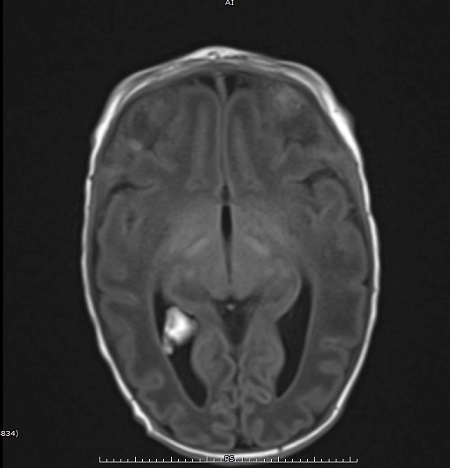

Con el objetivo de caracterizar mejor la lesión, se solicita RM, donde se evidencia un aumento de tamaño y engrosamiento del plexo coroideo derecho sugerente de plexitis como signo precoz de meningitis aguda, sin signos de ventriculitis.

Resonancia magnética. Aumento de tamaño y engrosamiento de plexo coroideo derecho sugerente de plexitis como signo precoz de meningitis aguda, sin signos de ventriculitis.